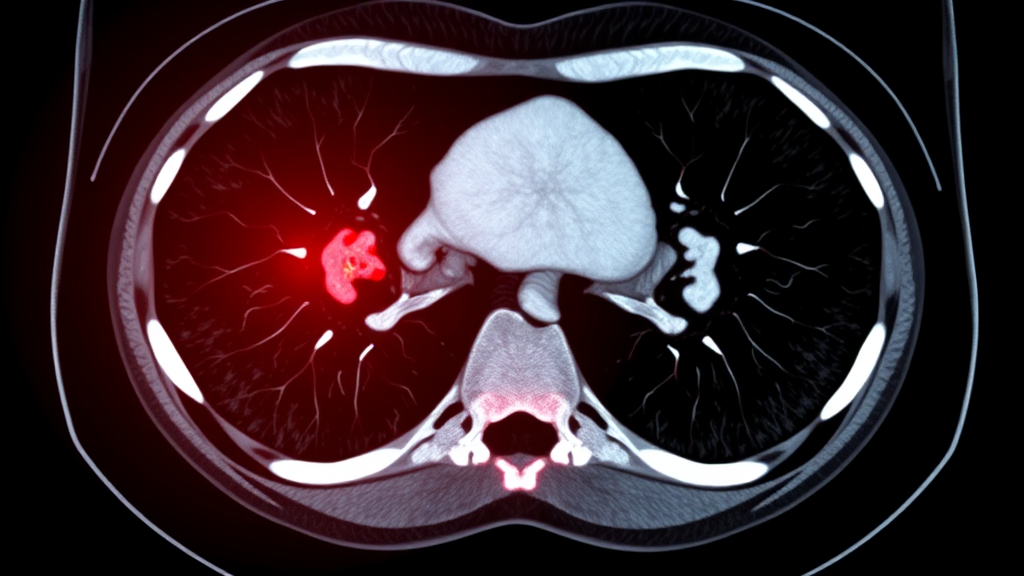

영상 검사의 중요성

복부 CT 촬영은 맹장염 진단에 가장 정확한 검사로 알려져 있어요. CT 촬영을 통해 충수돌기의 염증 여부, 주변 조직 상태 등을 자세히 확인할 수 있죠.

종합적인 진단

맹장염 진단은 증상, 신체 검사 결과, 혈액 검사 결과, 영상 검사 결과 등을 종합적으로 고려하여 이루어진답니다.